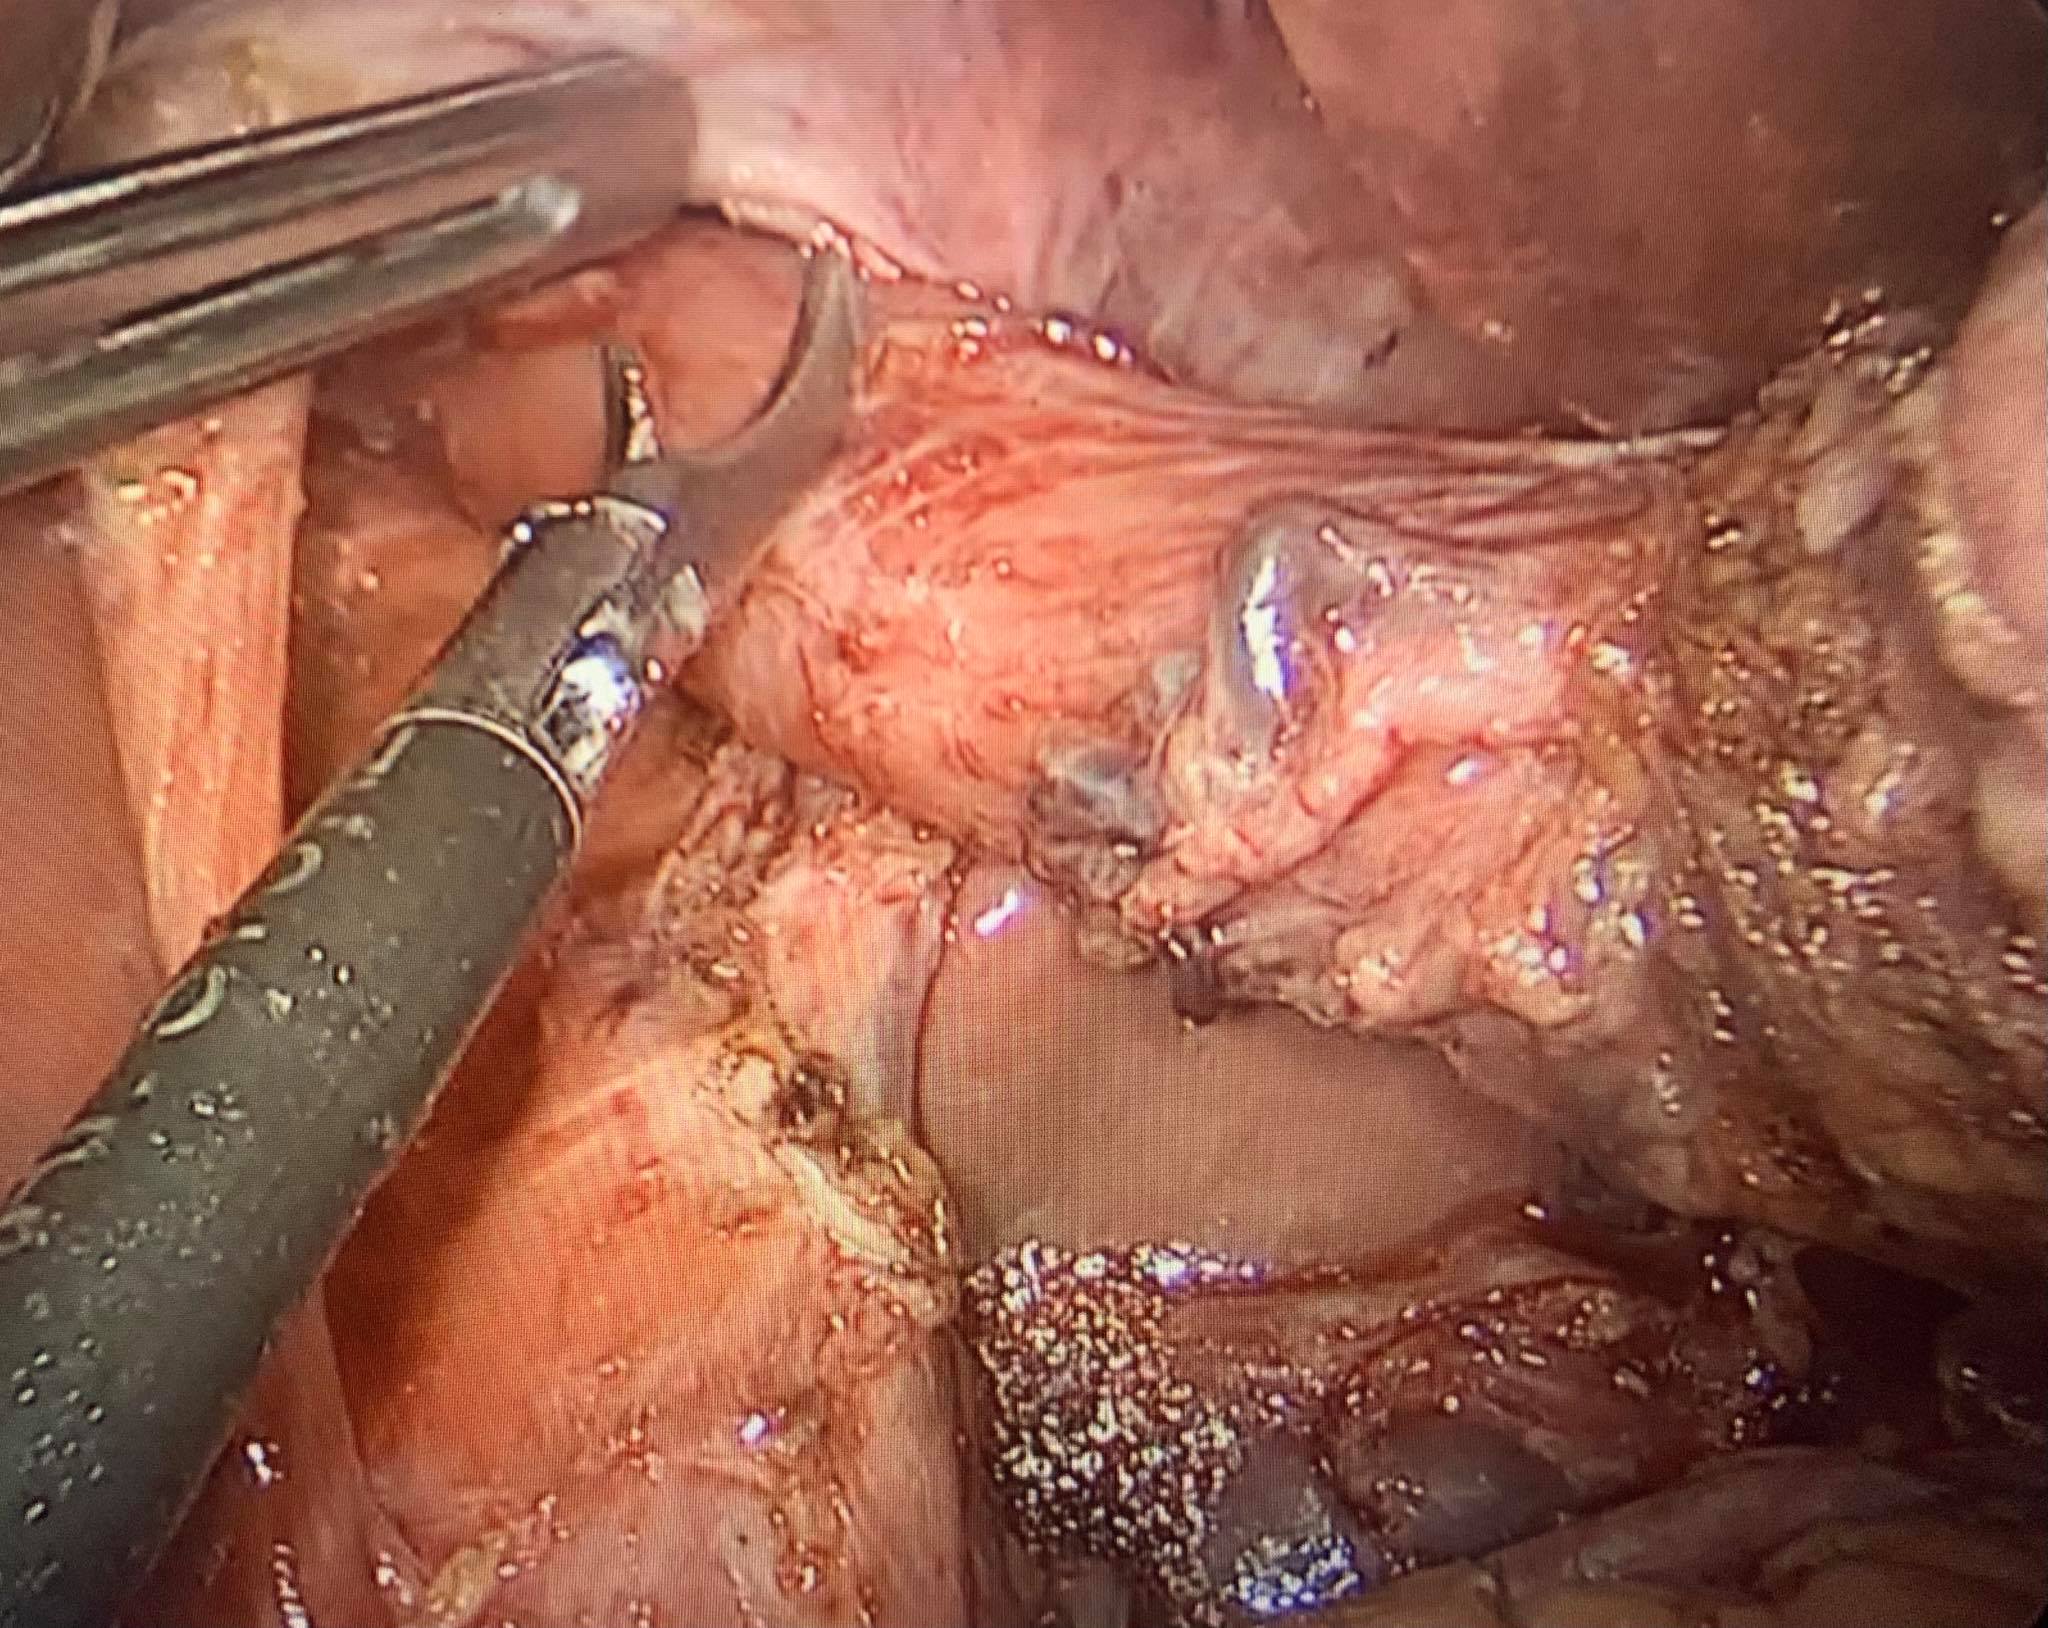

Hình 2: Nạo vét hạch và chuẩn bị cắt thực quản-tâm vị.